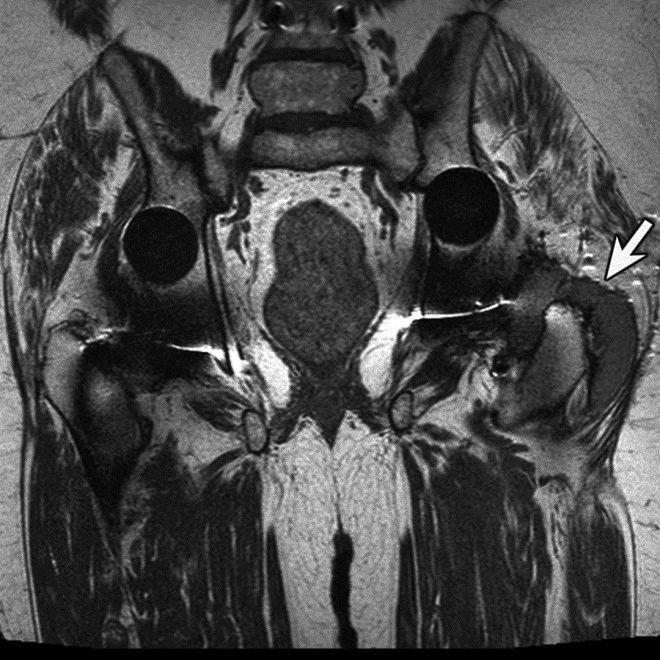

Adverse reaction to metal debris with anterior pseudotumor. Axial T1-weighted MR image shows large soft tissue mass (arrowheads) centered at the level of the lesser trochanter with involvement of the iliopsoas attachment site in a patient with metal-on-metal hip arthroplasty. Also note infiltrative involvement of the rectus femoris muscle.

On MRI, pseudotumors will appear as solid, cystic or mixed masses adjacent to and possibly communicating with the hip joint with potential intralesional or peripheral low T2 signal, reflecting metal deposition (Figure 24) (Chen, 2011). Solid lesions more commonly occur anteriorly, usually within the psoas muscle and may extend proximally into the pelvis (Figure 25) (Ostlere, 2011). Predominantly cystic lesions typically arise from the posterior joint space and may or may not demonstrate wall-thickening. Lateral lesions usually involve the trochanteric bursa and often communicate with the joint space. Differentiation of cystic and solid lesions may be difficult and the use of post-contrast imaging is not helpful for lesion detection, particularly due to surrounding metallic artifact. There may be involvement of the adjacent osseous structures with associated erosions, as well as the soft tissues, particularly the gluteal tendon attachments with resulting tendon disruption and muscle atrophy (Figure 26) (Anderson, 2011). In rare cases, the reactive process may involve pelvic or lower extremity arteries or the femoral nerve, particularly when occurring anteriorly (Clayton, 2008; Chen, 2011). At present, there is no established pathway for the management of metal-on-metal pseudotumor patients, and follow-up imaging may be performed to assess lesion progression before proceeding to revision, especially with small lesions or minor symptoms.